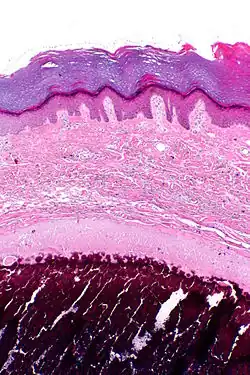

Micrograph of calcinosis cutis. The calcification is purple (bottom of image). H&E stain.